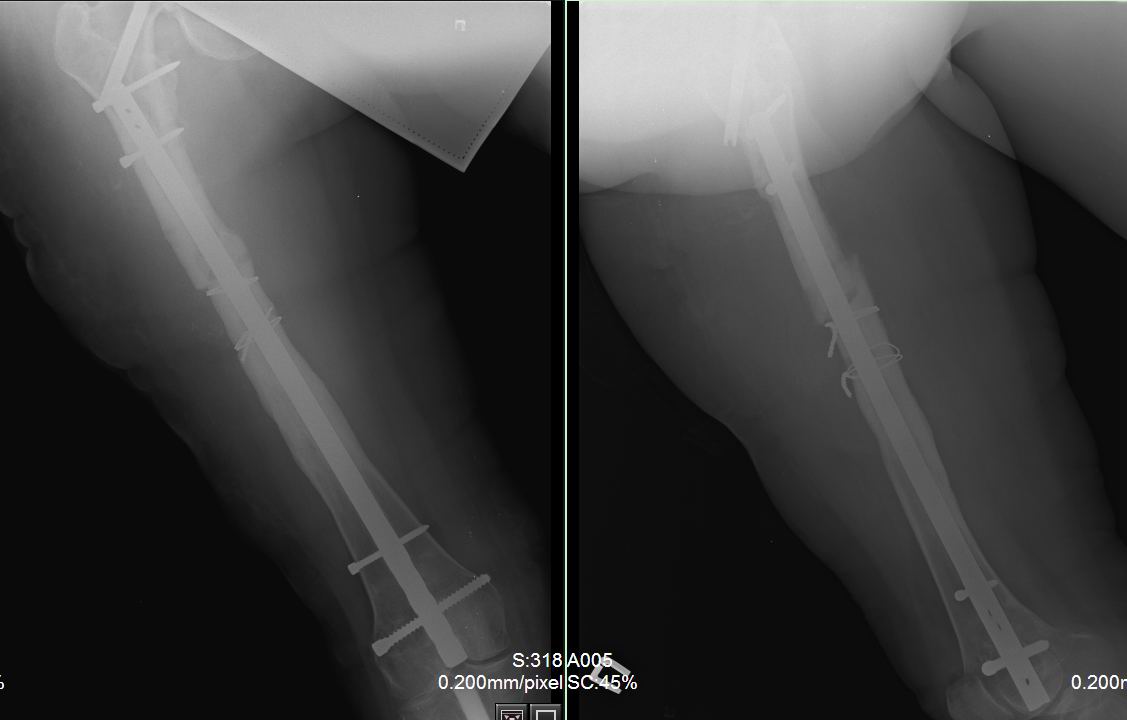

Вчера пациентка прооперирована. Как и ожидалось, основные трудности были с удалением металла. Удаление произведено из трех доступов: где пластина 8 см, блокирующие винты- 5 см, сам стержень 3 см.. Дольше всего пришлось извлекать  end  cap  у стержня, далее сломался 1 винт в пластине (долото в помощь, но аккуратно, только наружный кортикал, из внутреннего - выкручен). Рассверлил дистальный отломок до 14 мм, проксимальный до 13 мм. Стержень  ChM , диаметр12 мм. Долго существующая деформация бедра предопределила и положение стержня в проксимальном отломке – тесно к наружному кортикалу, надеюсь, до угрожающего конфликта не дойдет.